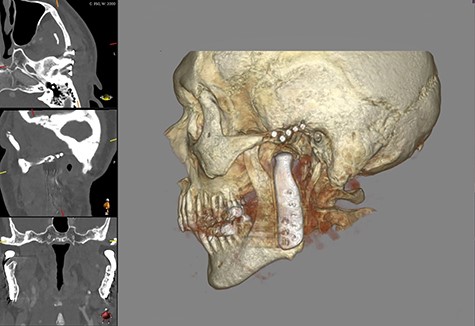

This report is about a 63-year-old patient suffering of bilateral deforming TMJ arthrosis (Wilkes-V) from a bilateral condylar fracture. In 2019 he presented himself to the Department of Oral and Maxillofacial Surgery, showing painful palpation above both TMJs and a severely decreased mouth opening (maximum interincisal distance of 1.5 cm). A computed tomography (CT) scan then revealed pathognomonic changes with flattening of the condyle and articular eminentia as well as partial ankylosis of the right TMJ (Fig. 1). Based on these findings, we decided for a bilateral TMJ-TJR. At this point, the patient only wanted one side replaced for the time being. After impressions were taken, plaster models were 3D-surface scanned and in combination with the CT dataset further processed by Zimmer-BiometTM (Warsaw, USA) for patient-specific TJR (PSI-TJR) fabrication. Another 3 months later, the TMJ-TJR of the right side could be carried out (Fig. 2). Postoperatively the patient received antibiotics for overall 7 days. Satisfied with the result, the patient requested reconstruction of the left TMJ 6 months later. With an improved mouth opening (2.8 cm), impressions were taken using an intraoral scanner. After PSI fabrication, the operation was carried out 9 months after (Fig. 3). Six weeks following surgery, the patient presented with a painful preauricular swelling on the left side, which was diagnosed as aseptic inflammation in the absence of erythema and pathologic joint puncture. Showing a periarticular edema, a broken screw and radial osteolysis around the drilling channels, a subsequent CT scan indicated the loosening of the ultra-high-molecular-weight-polyethylene (UHMWPE) fossa component (Fig. 4). In view of the long production time of new custom-made components and the damaged implant site, we decided to explant the fossa and to temporarily replace it with a non-fixed patient-specific spacer made of COPAL®-bone-cement (Fig. 5) (gentamicin and clindamycin additive) (Haereus; Hanau, Germany). The workflow included the surface scan of the original fossa-drilling template, the computer-aided design of a two-part press mould and the intraoperative fossa fabrication from COPAL®-bone-cement. With the use of a rubber elastic intermaxillary fixation, the vertical mandibular relation could be secured, painful movements and muscle shortening avoided and the risk of perioperative infection could be sufficiently minimized (Fig. 6). After 3 months without complications, the patient-specific COPAL® component could be removed and the new patient-specific UHMWPE fossa inserted within sufficiently regenerated bone (Fig. 7).

Intraoperative image showing the articular fossa (A) in combination with the articulating condylar component (B), the fixed ramus component (C) and the postoperative CBCT of the right side (D).

Shows postoperative CBCT after left TMJ replacement, 9 months after the right side.